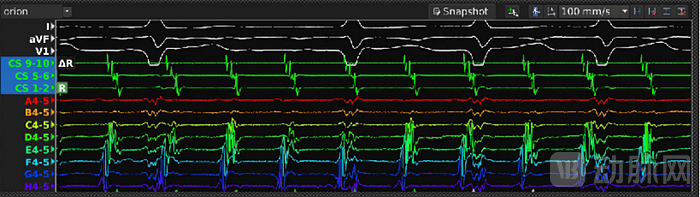

心航路医学自主研发的DePolar标测系统是目前全球首创的心脏“四维”标测系统,是与目前已经商业化的Carto/EnSite/Rhythmia/AcQMap等标测系统完全不同的下一代心脏标测系统。其最大特点在于,DePolar标测系统首次将磁电定位接触式标测和磁电定位非接触式标测在技术开发与临床应用层面都实现了无缝衔接,形成了统一的标测架构:

1.接触式标测系统,是目前Carto/EnSite/Rhythmia等传统标测设备都采用的一种规则性的心律失常标测系统/方法。该系统在进行术中激动顺序标测时,通过人为设定一个腔内参考电极为时间零点,并根据心腔内标测导管与心腔内壁接触记录的心脏内腔电位(通常为双极电位)计算局部激动时间和参考电极时间零点的时间差(单位为毫秒ms)。手术医生通过移动标测导管在心腔内壁各个位置都采集心腔内电位,并利用参考电极把心腔内各个位置发生在不同心跳的局部电激动时间拼凑出全心腔的激动顺序图,从而了解规则性心律失常的传播路径。采用多电极的高密度标测导管和自动标测算法可以大大提高标测的密度和精度,同时缩短标测时间。

接触式标测系统的不足之处在于,它所获得的激动顺序图是一个拼凑出来的图,要获得这个图,患者必须处于一个规则性且稳定的心律失常状态,并且这种心律失常必须能够维持足够的时间,以便医生在心腔内各个位置进行记录电位。

因此,接触式标测系统只能标测室上速/房速/房扑/室早/室速等规则性心律失常。然而,对于房颤患者,在发病时其心腔内心律失常呈现不规则性,并且随时在发生变化,接触式标测系统对这种紊乱多变的心律失常就无能为力了。

2.非接触式标测系统,是由Graydon Beatty博士率先提出的心律失常标测技术,特点在于使用独创的非接触式标测导管,并结合独家的心电源标测算法,在进行心律失常标测时,无需与心腔内壁接触,即可即时计算全心腔内的激动时间,从而实现对心律失常的全心腔实时标测。这也是全球唯一能够对非规则性心律失常,如房颤, 进行标测的技术。

通过将磁电定位接触式标测技术与磁电定位非接触式标测技术相结合,DePolar标测系统不但可以实现室上速、室速、房速等规则性心律失常的标测(磁电双定位接触式标测,与Carto/EnSite/Ryhthmia等传统标测系统功能一致),而且还可以实现房颤等非规则性心律失常的标测(磁电双定位非接触式标测,全球唯一),因此,它将是世界上第一个可以实现"一跳全心腔,时空同步标"的标测系统,对于未来房颤标测将是一个非常有利的临床应用工具。